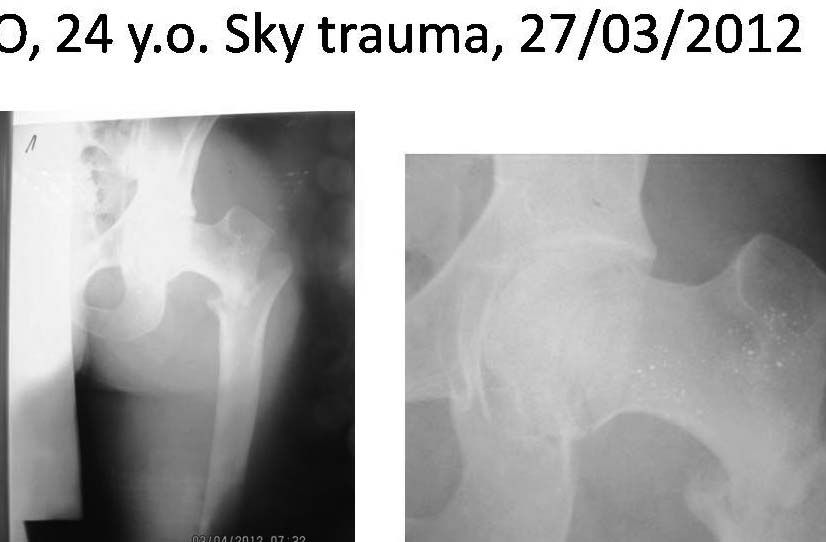

Коллеги! Хотелось бы посоветоваться по тактике лечения больного.Больной 24 лет, травму получил катаясь на горных лыжах. На рентгенограммах вертельный перелом. Но при детальном изучении снимков появилось подозрение на перелом головки бедра. Это побудило выполнить КТ. На КТ перелом заднего края вертлужной впадины.Планируем проксимальный стержень. А вот с вертлужной впадиной вопрос. Синтезировать или консервативно. "За операцию" внутрисуставной перелом, с вдавлением фрагмента суставной поверхности. "Против" смещенный фрагмент в задне-нижнем квадранте и в меньшей степени нагружаем... С ув Коробушкин Г.